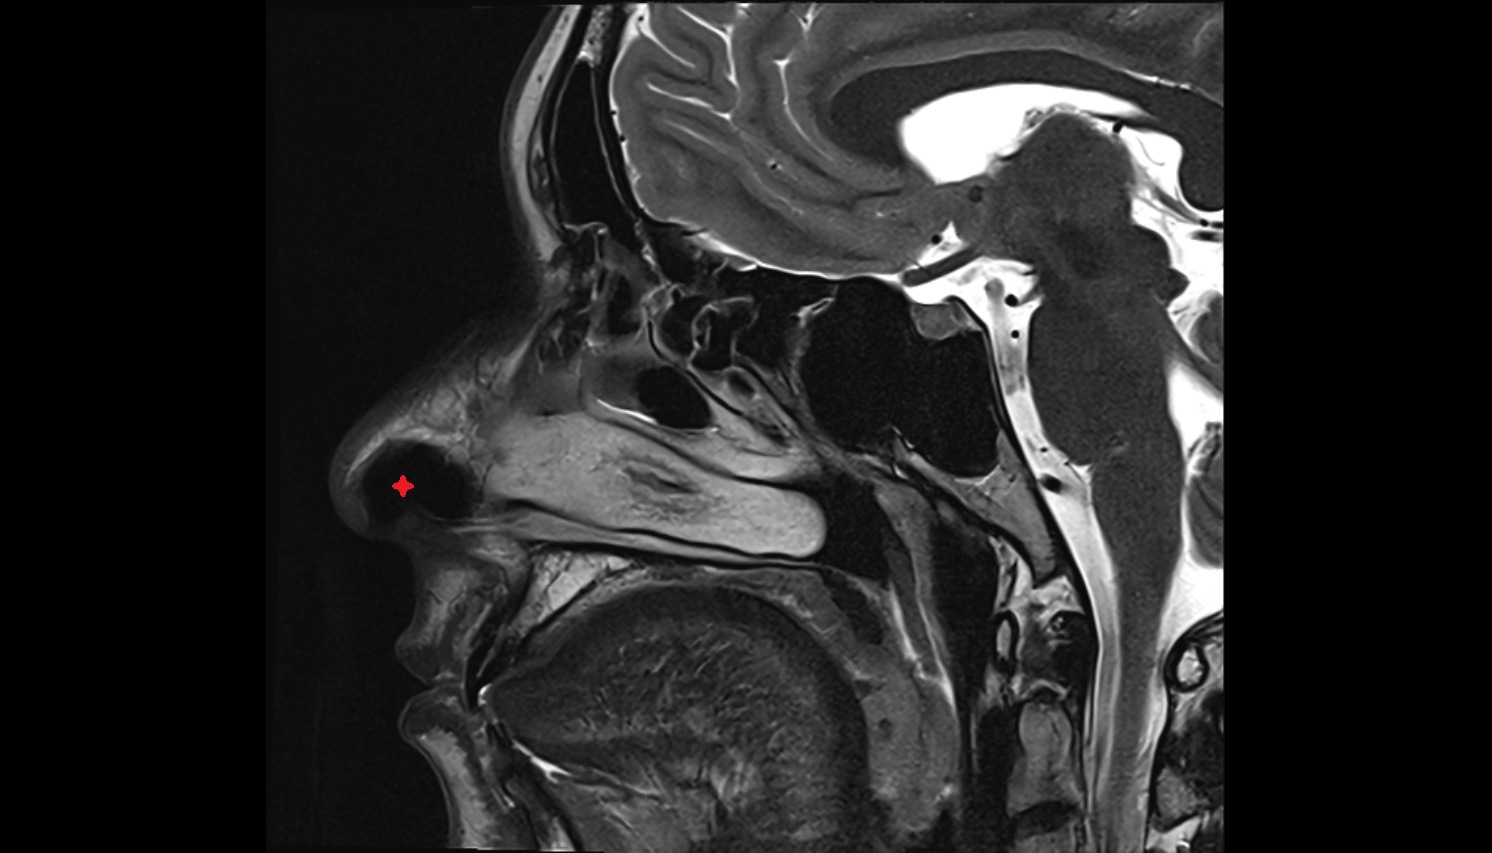

- Nasopharynx